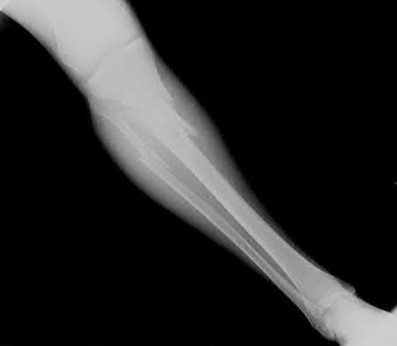

1. # A 32-year-old male sustains the injury shown in Figure A and undergoes treatment as shown in Figure B. Following placement of this implant, what is the best technique to confirm it is not too proud proximally?

The safe zone for tibial nail placement as seen on radiographs is just medial to the lateral tibial spine on the anteroposterior radiograph and immediately adjacent and anterior to the articular surface as visualized on the lateral radiograph.

Tornetta et al specifically located the safe zone for nail entry in a study using fresh frozen cadaver knees. The authors found that the safe zone for nail placement is located 9.1+/-5 millimeters lateral to the midline of the plateau and three millimeters lateral to the center of the tibial tubercle. The width of the safe zone averaged 22.9 millimeters and was as narrow as 12.6 millimeters.

The starting point of the of the nail can be best viewed on the lateral knee radiograph, an example of which is shown in Illustration A. Illustration B shows the "sweet spot" for nail insertion as defined by Tornetta.